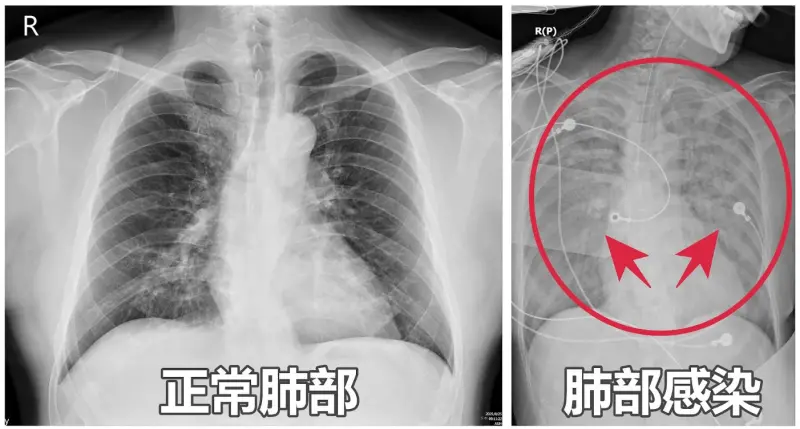

一位65歲女性日前因嗜睡、咳嗽、全身無力及胃口不佳掛急診,家人反映患者像「靈魂出竅」,測量血氧後只剩下90%,X光更發現「雙肺白掉一大片」,評估是肺炎惹禍,緊急送至加護病房觀察照顧,治療一週後順利出院。

謝逸安指出,疫情肆虐,許多民眾往往聞肺炎色變,除了新冠肺炎外,流感、呼吸道融合病毒(RSV)及肺炎鏈球菌等,都是常見社區型肺炎的呼吸道病原,尤其60歲以上長者、孕婦、兒童以及免疫力較弱的慢性病患,更是感染高風險族群,往往一感冒就造成「大白肺」。